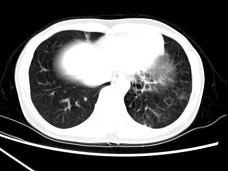

问题 女,30岁,咳痰,咯血,请结合影像图像选择最可能的诊断为 ( )

选项 A、间质性肺炎 B、肺结核 C、支气管扩张并感染 D、支气管囊肿 E、肺部感染

答案 C